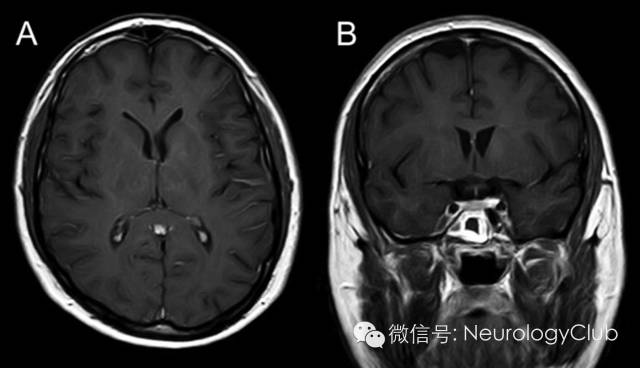

30岁男性,表现为面-臂肌张力障碍发作(faciobrachial dystonic seizures,FBDS)。发作期和发作间期的脑电图正常。脑脊液化验无殊。头颅MRI示左侧尾状核和苍白球强化病灶(图1)。血清LGI-1(富亮氨酸胶质瘤失活1蛋白)抗体阳性。全身CT扫描未发现恶性肿瘤。患者行5个周期的血浆置换后再接受长期的激素治疗,完全恢复。5月后复查头颅MRI,发现病灶强化信号减弱(图2)。LGI-1是一种与电压门控钾离子通道相关的分泌蛋白,在新皮质与海马区高度表达。LGI-1突变见于合并听觉症状的常染色体显性遗传颞叶癫痫(autosomal dominant partial epilepsy with auditory features,ADPEAF)。本例患者无ADPEAF的临床症状。关于FBDS是一种癫痫发作还是肌张力障碍仍存在争论。本例患者基底节区受累可与这一争议相关。

图2:治疗后复查增强MRI